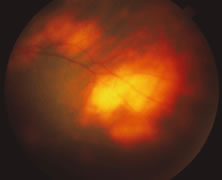

The ARN patient typically presents with progressive visual blurring in one or both eyes occurring over several weeks. These patients often are initially treated with corticosteroids, antitoxoplasmosis drugs, and other medications before arriving at the correct diagnosis. Examination reveals a prominent anterior uveitis that may be granulomatous or nongranulomatous (Fig. 1). Inflammatory signs may be prominent and cause severe pain (Fig. 2). The uveitis may be diffuse and so severe that it causes proptosis. These signs, and the diffuse vitreitis that makes the view of the retina difficult, may contribute to the high degree of delayed and/or misdiagnosis that occurs in the early stages of the disease. Significant vitreous cellular infiltration is seen in the presence of retinitis that is manifest by opacification of the retina, often most prominently in the periphery. Posterior pole involvement may include retinitis, as well as inflammation of the optic nerve head. Optic neuropathy might be the first sign of ARN with subsequent development of other retinal manifestations.8 Ultrasonography and computed tomography (CT) might be helpful in cases of ARN associated with optic nerve edema revealing enlargement of the optic nerve sheath.9 Even in ARN patients who are not immunocompromised and who have no clinical evidence of encephalitis, magnetic resonance imaging of selected cases has shown lesions of the lateral geniculate, optic tracts, and chiasma, which suggests that the virus spreads through the central nervous system (CNS) by axoplasmic transport from the retinal ganglion cells.10 A secondary retinal vasculitis is common, often accompanied by a mild number of retinal hemorrhages. Days to weeks after onset of the infection, the discrete peripheral lesions typically coalesce into a white or yellow ring of infected retina, and the associated vasculature is obliterated (Fig. 3). Necrotic retina desquamates into the vitreous resulting in vitreous sheets.3,6 Eventually, most untreated eyes can be expected to develop retinal detachment resulting from development of multiple full-thickness retinal breaks accompanied by traction or exudation.11 Giant retinal pigment epithelial tears have also been reported.12

A variable number of eyes, up to 75%, develop retinal detachments (Fig. 5). Prophylactic laser for demarcating the areas of active retinitis from normal retina has been advocated to create chorioretinal adhesions that prevent retinal detachments around sites of retinal break formation (which usually occur at the zone between affected and healthy retina). Han and associates43 reported five cases treated with prophylactic laserpexy in addition to antiviral, steroid, and antiplatelet therapy. After 15 months of follow-up, no retinal detachments were noted. Sternberg and coworkers44 described a 75% decrease in the rate of retinal detachment using prophylactic photocoagulation. Some have advocated the creation of a “new ora serrata” by applying confluent rows of laser burns posterior to the areas of retinitis. However, if traction forces from vitreous organization, epiretinal membrane (ERM) formation, or proliferative vitreoretinopathy develop as they commonly do, the contractile forces will be able to overcome any increased chorioretinal adhesion created by the laserpexy. However, McDonald and associates45 reported failure of prophylactic peripheral laserpexy to prevent retinal detachment in ARN patients. In addition, many cases of ARN result in a severe vitritis, limiting the view for a planned laserpexy (Fig. 6). Therefore, vitrectomy with endolaser and concomitant encircling of the eye with a scleral buckle to reduce traction may be required in some patients.46,47 Decisions relating to the need for scleral buckling to support retinal breaks and the use of silicone oil or long-acting gases to repair retinal detachments should be made by an experienced vitreoretinal surgeon.40,48 Selection of cases to undergo operation should be made with consideration given to optic nerve function, visual potential, and medical control of retinitis.